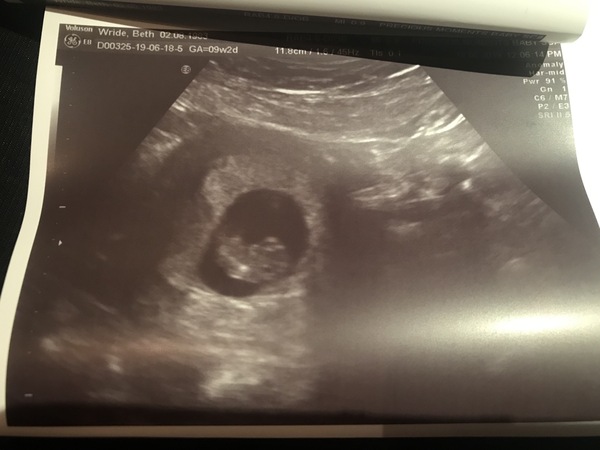

beth3735 · 18/06/2019 18:15

9+2 weeks today, everything was all as it should be with a heart rate of 168. My impatience got the better of me and made me book the appointment for today 💕

@NoMoreFastCars82 thank you, I still have to have my scan that’s booked for Sunday as my partner couldn’t make today as it was spur of the moment 🤦🏻‍♀️😂 I love seeing people’s scan pictures, especially now our babies are looking more like babies 💕